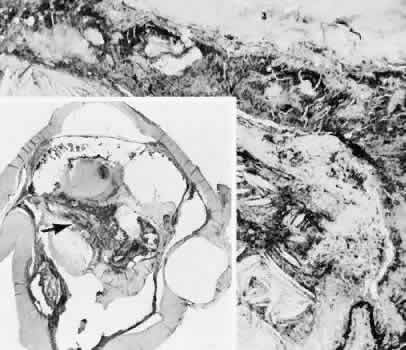

Expulsive choroidal hemorrhage (Fig. 30) is a rare catastrophic complication often resulting in total loss of the eye.93 The site of hemorrhage is probably a sclerotic choroidal arteriole where the vessel crosses the suprachoroidal space from the scleral canal. The sudden hypotension after surgical penetration of the globe causes a bending and then a rupture of the arteriole.94 Although most hemorrhages are massive and immediate, they occasionally are delayed, and some may not occur for days or weeks after surgery. Delayed choroidal hemorrhage may occur at the time of corneoscleral suture removal,95 because of clinically unapparent wound dehiscence or as a result of perforation of a corneal ulcer.

Fig. 30. A case of expulsive choroidal hemorrhage. A. Expulsive choroidal hemorrhage occurred 3 weeks after cataract surgery at the time when a limbal suture was removed. The intraocular pressure was reduced enough to allow shearing forces in the superficial choroid to tear an arteriole resulting in a high-pressure hemorrhage. B. In another case enucleated shortly after cataract extraction because of expulsive hemorrhage, accumulated blood can be identified in the suprachoroidal space. Because of the loose attachment of the choroid to the sclera, all intraocular contents were displaced toward the cataract wound. (Hematoxylin-eosin stain; × 3.)

Histologically, massive choroidal hemorrhagic detachment is associated with a retinal detachment. The retina and choroid may herniate through the scleral wound. A ruptured ciliary artery may be found in the suprachoroidal space.